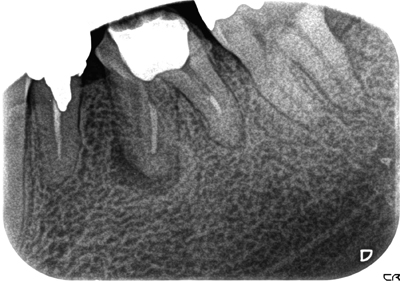

症例3【50代男性】左下第一大臼歯の根尖病巣。

根管内の殺菌・消毒を約3ヶ月間行うことにより、病巣はほぼ消失、硬線が明瞭に見える。

治療前

治療後(14ヶ月後)